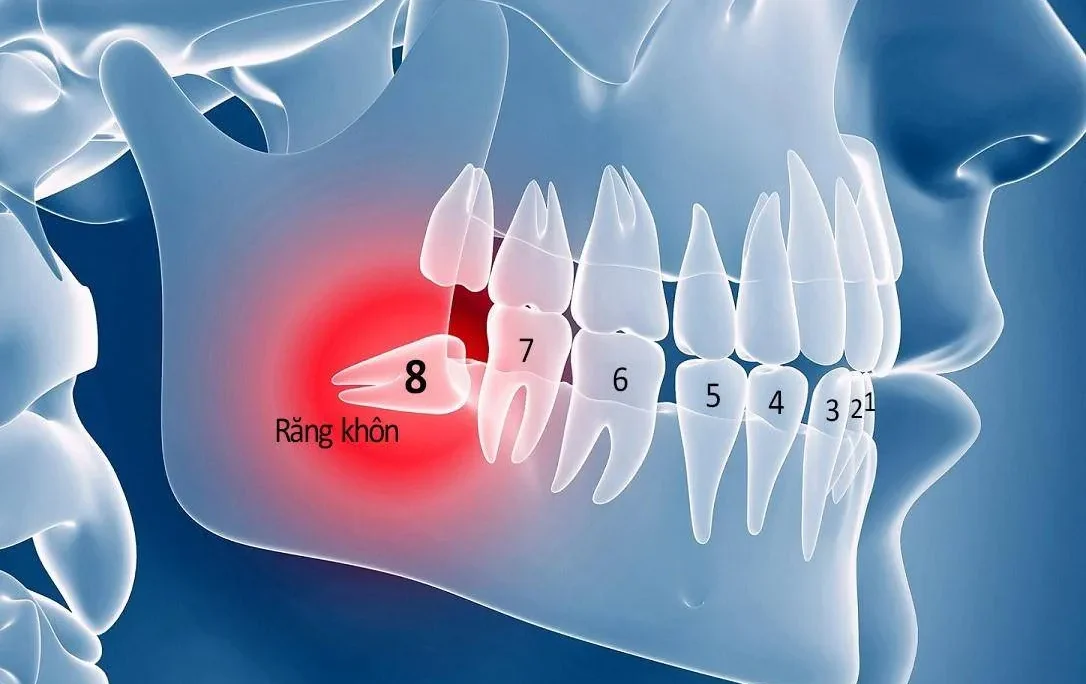

Nhiễm trùng sau Nhổ răng: Trường hợp nhổ răng khó, nhổ răng khôn kẹt, hoặc nhổ răng trong điều kiện vô trùng không đảm bảo, vi khuẩn có thể xâm nhập trực tiếp vào xương hàm.

- Xử lý Triệt để Nguyên nhân: Bác sĩ cần nhổ bỏ những chiếc răng bị nhiễm trùng nặng là nguồn gốc gây bệnh, điều trị tủy các răng còn khả năng giữ lại, và kiểm soát viêm nha chu.